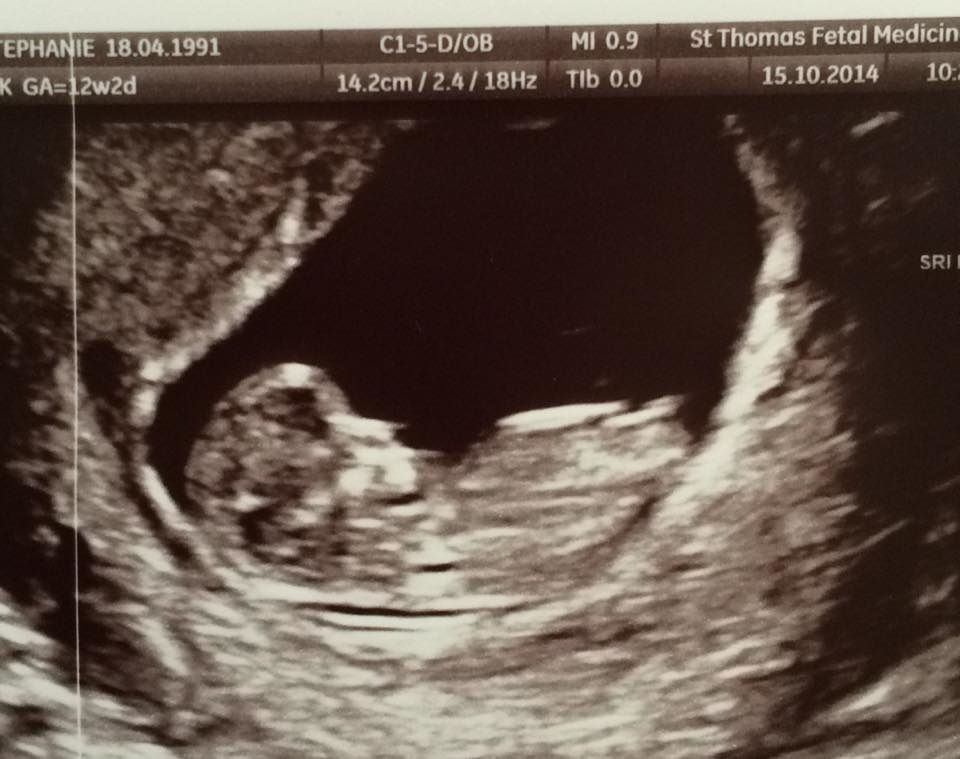

I'm 14+0 today and this picture was taken at the 12 weeks scan at 11+6 weeks.

Any guesses? :) Was somewhat hoping for a boy but got that strange feeling since the very beginning it's gonna be a girl...

Might be wrong though. What do you think?